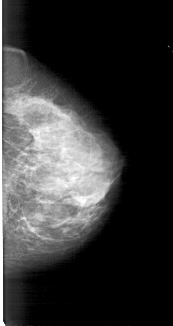

A_1183_1.LEFT_MLO

LEFT_MLO LINES 5491 PIXELS_PER_LINE 2926 BITS_PER_PIXEL 12 RESOLUTION 43.5 OVERLAY